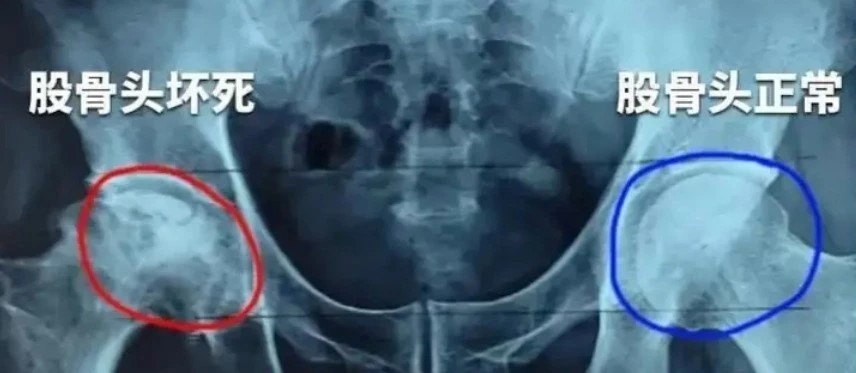

股骨頭壞死(Osteonecrosis of the femoral head,ONFH)又稱缺血性股骨頭壞死,是骨科中常見的難治性疾病,主要病因是股骨頭血液供應遭到破壞,導致骨髓成分減少與骨細胞死亡,最終股骨頭壞死塌陷,引起髖部疼痛,降低患者的生活質量。

ONFH高發于20-40歲中青年人,其自然進展快,如不干預治療,多數患者可在1-4年內發展為股骨頭塌陷、髖關節繼發性骨性關節炎,進而需要髖關節置換。